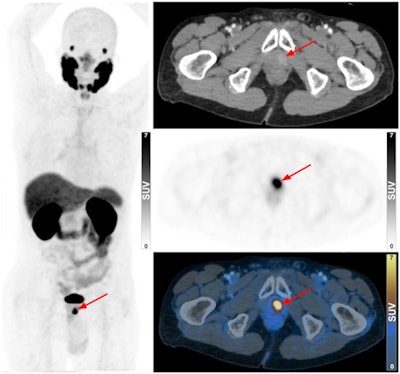

Ga-68 PSMA-11 PET/CT of an 84-year-old man (no biopsy) with rising PSA levels. Focus of increased uptake was identified at left apex of prostate (arrow), indicating localized disease. Image courtesy of the Journal of Nuclear Medicine through CC BY 4.0.

Ga-68 PSMA-11 PET/CT of an 84-year-old man (no biopsy) with rising PSA levels. Focus of increased uptake was identified at left apex of prostate (arrow), indicating localized disease. Image courtesy of the Journal of Nuclear Medicine through CC BY 4.0.According to the analysis, the PET/CT scans revealed at least one avid lesion in all patients: 36 had localized disease, 25 patients were categorized as having locally advanced disease, and 39 patients had advanced disease. The median blood prostate-specific antigen (PSA) level of the group was 22.6 ng/mL (with PSA levels below 4.0 ng/mL considered normal).